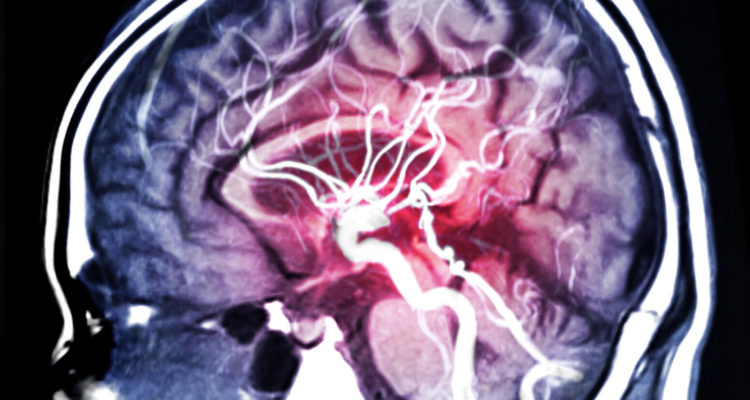

Інсульт може виявлятися неочевидними ознаками

За словами британського лікаря Рейчел Уорд (Rachel Ward), однією з ознак інсульту головного мозку може бути гикавка.

Терапевт зі Сполученого Королівства виступила в ЗМІ з поясненнями про ті неочевидні ознаки, якими може проявлятися інсульт. Також Рейчел Уорд нагадала про “класичні” ознаки цього небезпечного захворювання мозку: до них відносяться лицьова асиметрія, нездатність одночасно підняти обидві руки, нечленороздільна мова, оніміння частин тіла.

Говорячи про можливі неочевидні ознаки інсульту мозку, терапевт порадила не випускати з уваги наступні стани.

Гикавка. Відомі випадки, коли напередодні інсульту пацієнти гикали протягом доби або довше. Таке можливо через переривання згустком крові нормального кровопостачання задньої частини мозкового стовбура.

Головний біль. При інсульті вона стає толерантною до дії анальгетиків.

“Якщо голова немов розколюється, а таблетки ніяк не допомагають, викликайте швидку”, – порадила Рейчел Уорд.

“Чуже” тіло. Постраждала людина стає незграбною, тіло “відмовляється” підкорятися, виникають некеровані рухи – все це результат порушення в роботі мозкових центрів рівноваги.

Нудота. Вона може бути дуже сильною, супроводжуватися запамороченням.

Затуманений зір. Раптово зір перестає бути чітким, картинка в очах “розмивається”.